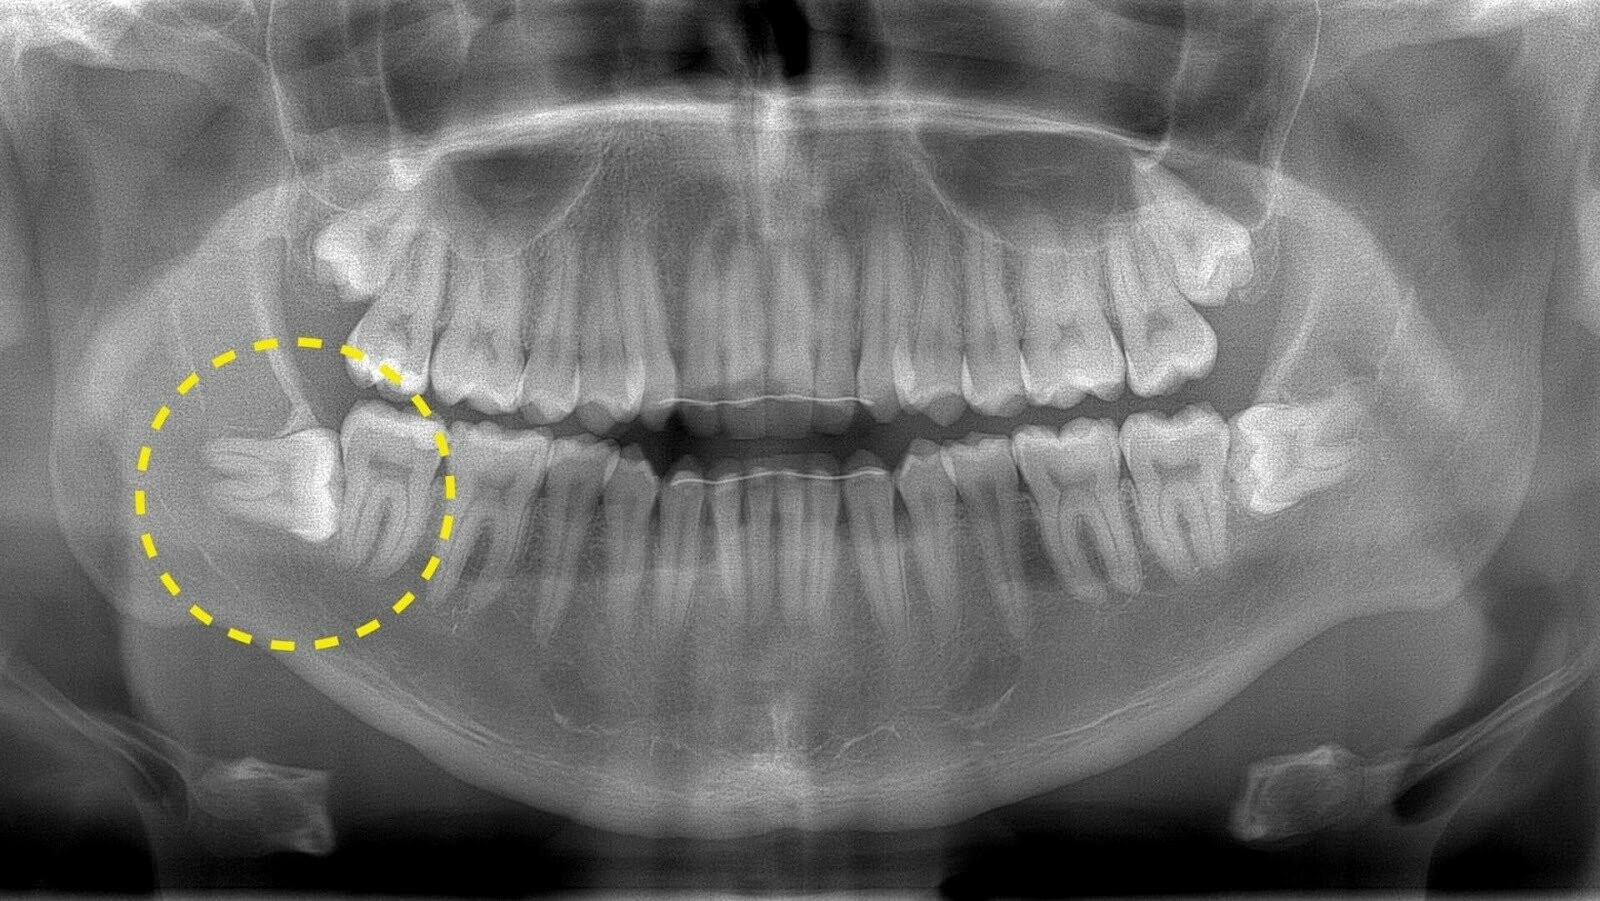

Зуб мудрості, це такий зуб, що рідко викликає позитивні враження. Йдеться про восьмий зуб на кожній стороні щелепи. Він прорізується останнім, як правило, це стається років у двадцять п’ять. Оскільки не вистачає місця для того, щоб ці зуби росли нормально, багато хто задумується про видалення зуба мудрості задля вирішення такої проблеми. Інакше наявність кутнього зубу призводить до болю, різних ускладнень, таких як неправильне прорізування.

Коли йдеться про операцію по видаленню зубу мудрості, то це проводиться у кілька етапів:

- Спочатку хірургом виконується акуратний розріз ясен;

- Далі формується доступ у кістці до зубного кореня;

- Це поділяється за допомогою бормашини, витягується по одному;

- Отвір у кістці закривається;

- На ясна накладаються шви.